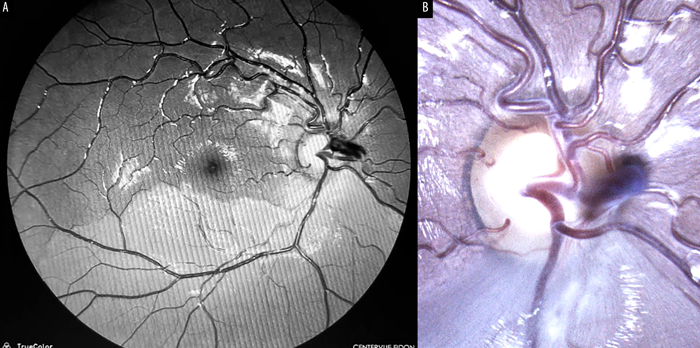

Paciente masculino sano de 10 años que consultó refiriendo un escotoma visual altitudinal superior de su ojo derecho (OD) de 24 horas de evolución sin otros signos ni síntomas asociados. Al examen oftalmológico se constató una agudeza visual de 10/10 en ojo derecho e izquierdo sin corrección óptica. Tanto la biomicroscopía como la presión intraocular eran normales. Al examen de fondo de ojos se evidenció en su OD un AVP y un blanqueamiento de la retina temporal inferior con atenuación de la vasculatura correspondiente al territorio afectado (fig. 1). La retina del ojo izquierdo (OI) se encontraba dentro de parámetros normales. Cabe destacar que era su primera consulta en la institución y que tampoco se contaba con retinografías previas del paciente.

Figura 1. Retinografía. A) AVP arterial y blanqueamiento de la retina temporal inferior con atenuación de los vasos en el territorio comprometido. B) AVP con mayor magnificación y comienzo de blanqueamiento retinal.